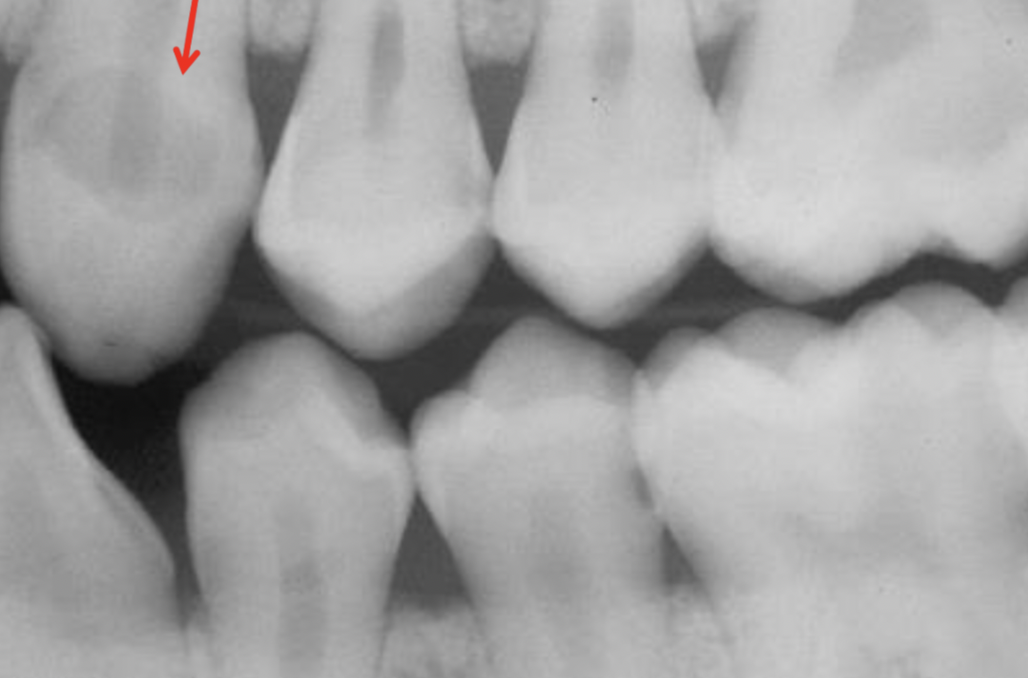

Q

Classify the caries

A

Root surface caries (RSC)